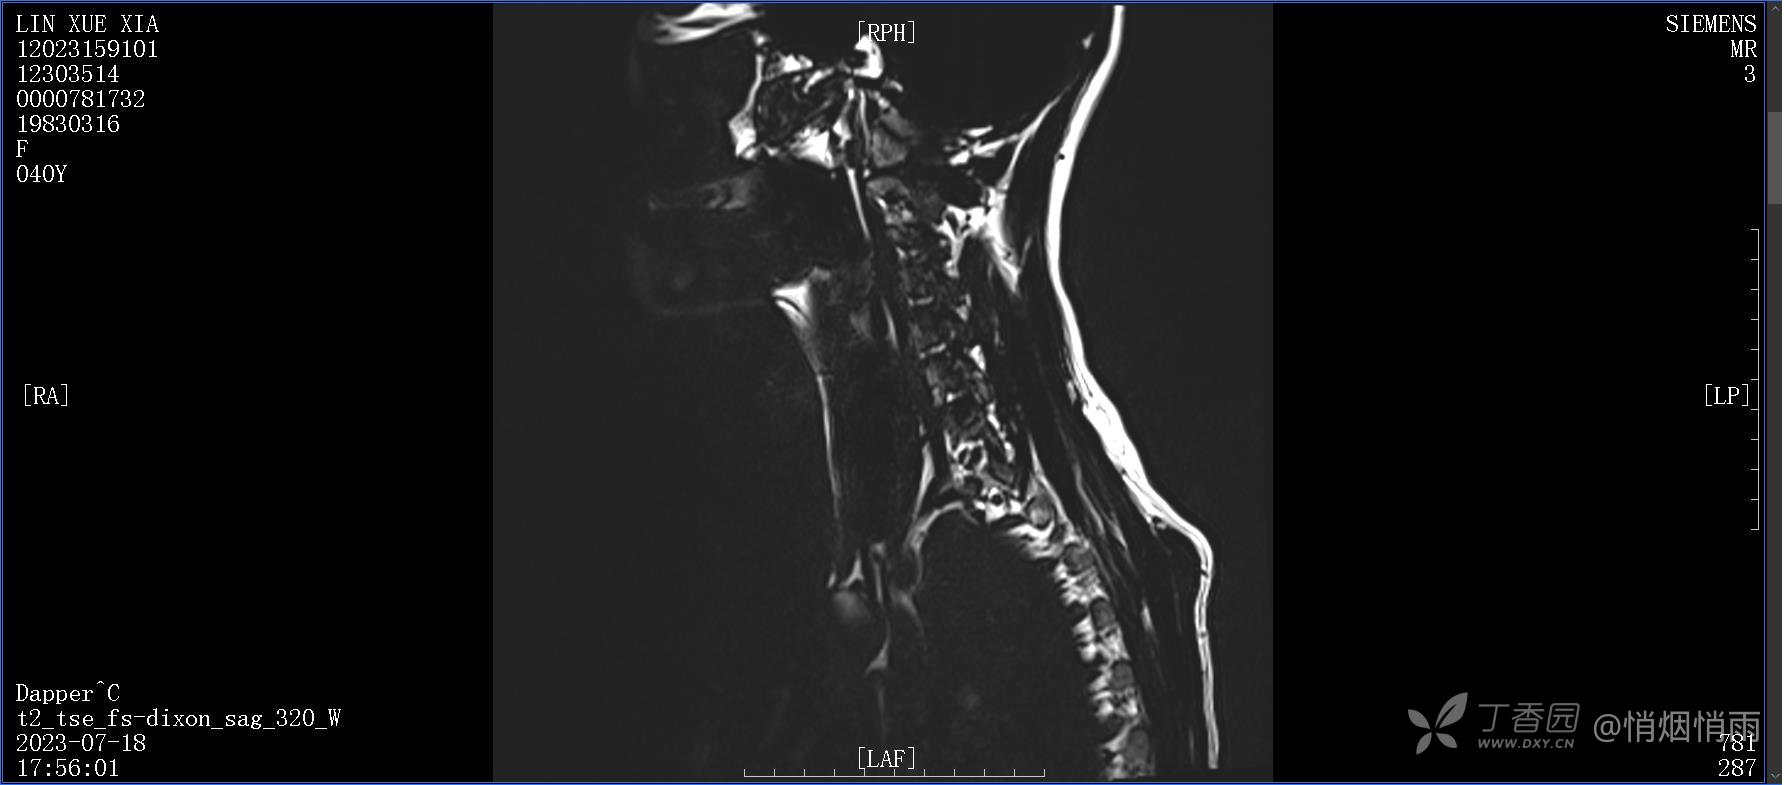

NeurothinkerZ 推荐患者女性,40岁,因右肩背部疼痛班活动受限4日余入院(2023-07-17)。

病史:入院前4天无明显诱因突然感右肩背疼痛伴随活动受限,自行口服依托考昔、艾瑞昔布等药物治疗,院外应用肩关节局部手法按摩等,均无明显改善。外院门诊诊为颈椎病。自诉既往多次“胸椎小关节紊乱”于当地诊所行手法按摩,治疗后好转,否认慢性疾病病史、外伤史、手术史,诉青霉素过敏,无其他药物食物过敏史,否认吸烟史、饮酒史,月经正常,经量正常。

目前的诊断,暂时依据辅助检查诊为肩袖损伤,但是患者疼痛的性质和特点,却不是单纯的肩袖损伤所致。考虑过胸廓出口综合征,但是该疾病会出现肩胛区的疼痛吗?(由于考虑到费用的问题,没再进行下一步的检查)带状疱疹会有如此的症状吗?